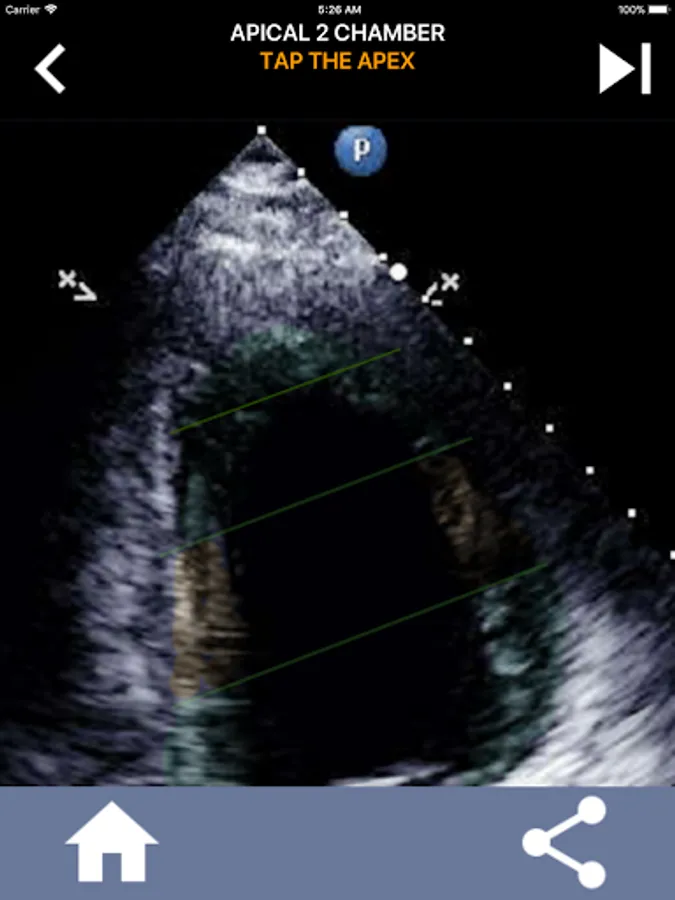

Understanding the AHA (American Heart Association) heart segments is of utmost importance for a cardiac sonographer to effectively communicate with the cardiologist who writes the report. By knowing the specific anatomical regions and their corresponding segments, the sonographer can accurately describe and communicate any abnormalities or findings, ensuring clear and concise communication between both professionals.

This understanding becomes particularly crucial when the cardiologist seeks to ascertain the precise location of a problem or when the on-call physician identifies an issue within a specific region, prompting the sonographer to accurately display the corresponding segment, such as the mid-inferior wall. Thus, possessing a comprehensive grasp of the AHA heart segments is essential skill set.

This app will test your knowlegde using actual echo images, which I often find to be the best teaching method.